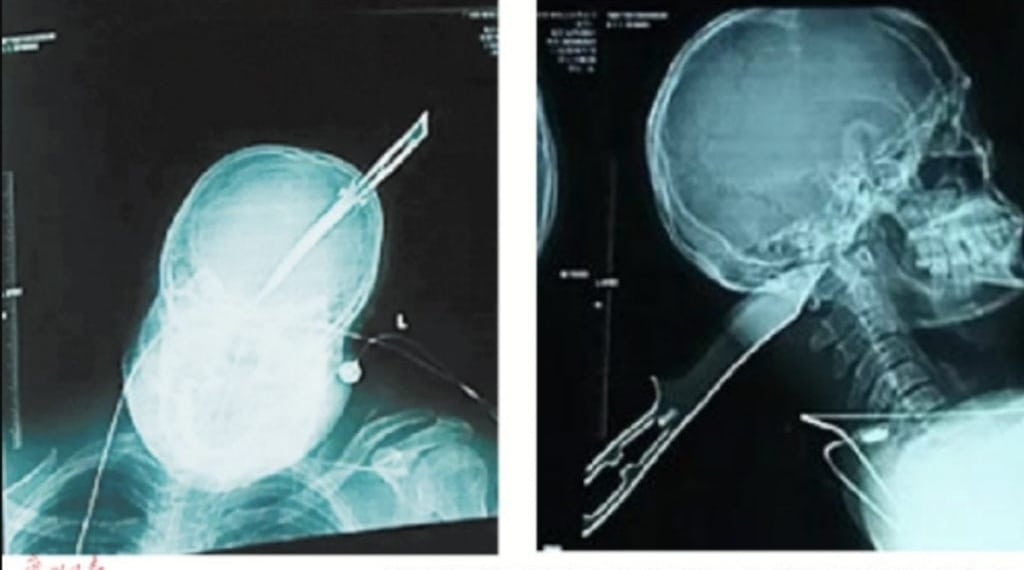

Ảnh siêu âm cho thấy con dao đâm khá sâu vào đầu anh Tần.

Vì vậy, anh đã quyết định tự xử lý. Tần đã lái xe máy đến đồn cảnh sát gần nhất cách đó 20 phút trong khi con dao đang cắm sâu 8 cm trong đầu. Sau đó, anh được đưa đến bệnh viện và ngay lập tức vào phòng phẫu thuật. Sau 5 tiếng đồng hồ, các bác sĩ đã lấy được con dao cắm xuyên qua đầu anh và chăm sóc vết thương.

Các bác sĩ nói đây thực sự là một phép màu khi anh Tần có thể sống sót sau sự việc kinh hoàng này. May mắn là hộp sọ đã giúp cố định con dao tại chỗ, ngăn sự xuất huyết nhanh. Ngoài ra, dù mũi dao đâm xuyên qua não, nó đã không làm tổn hại bất kỳ bộ phận quan trọng nào. Nếu con dao xuyên sâu hơn một hoặc hai cm, anh Tần có thể đã tử vong ngay tại chỗ.